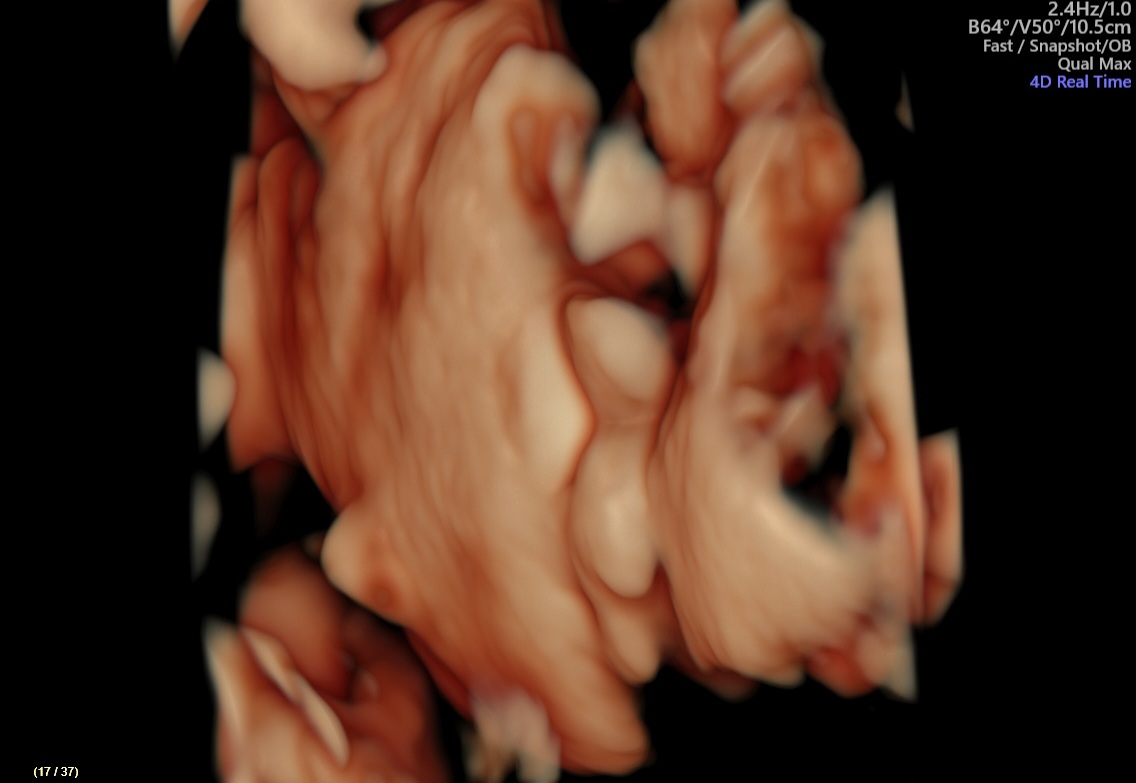

bola som na sono.

Bude to chlapec alebo dievča?

najideálnejšie je vidieť obraz v pohybe. Ak je fotka zameraná priamo na genitál, tak je to chlapček 🙂